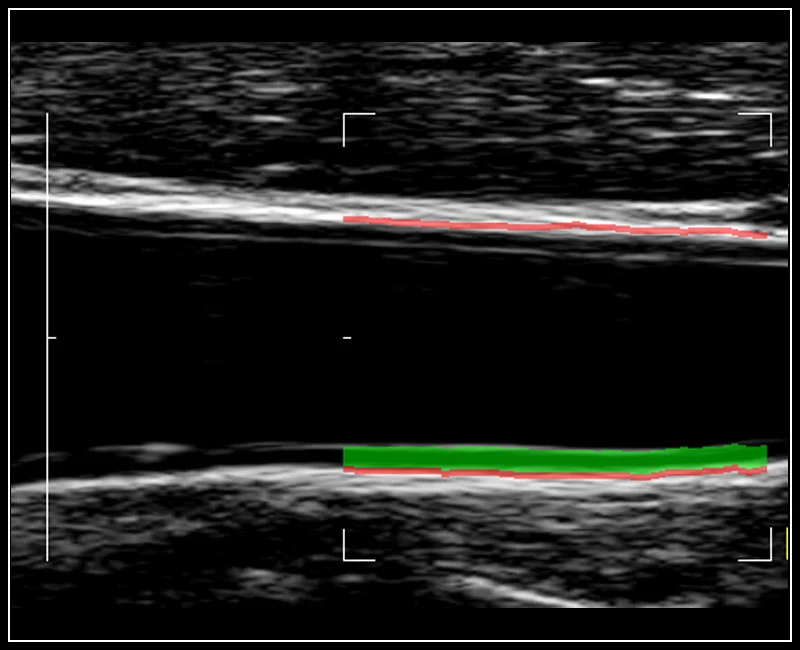

MyLab™9 Platform - QIMT Intima-media thickness quantification based on radio frequencies in real-time studies

MyLab™9 Platform - QIMT Intima-media thickness quantification based on radio frequencies in real-time studies